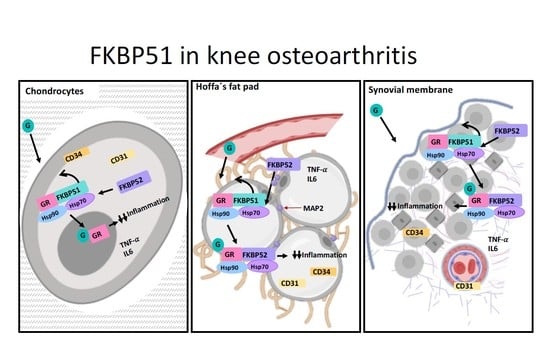

3. Results

4. Discussion

5. Conclusions